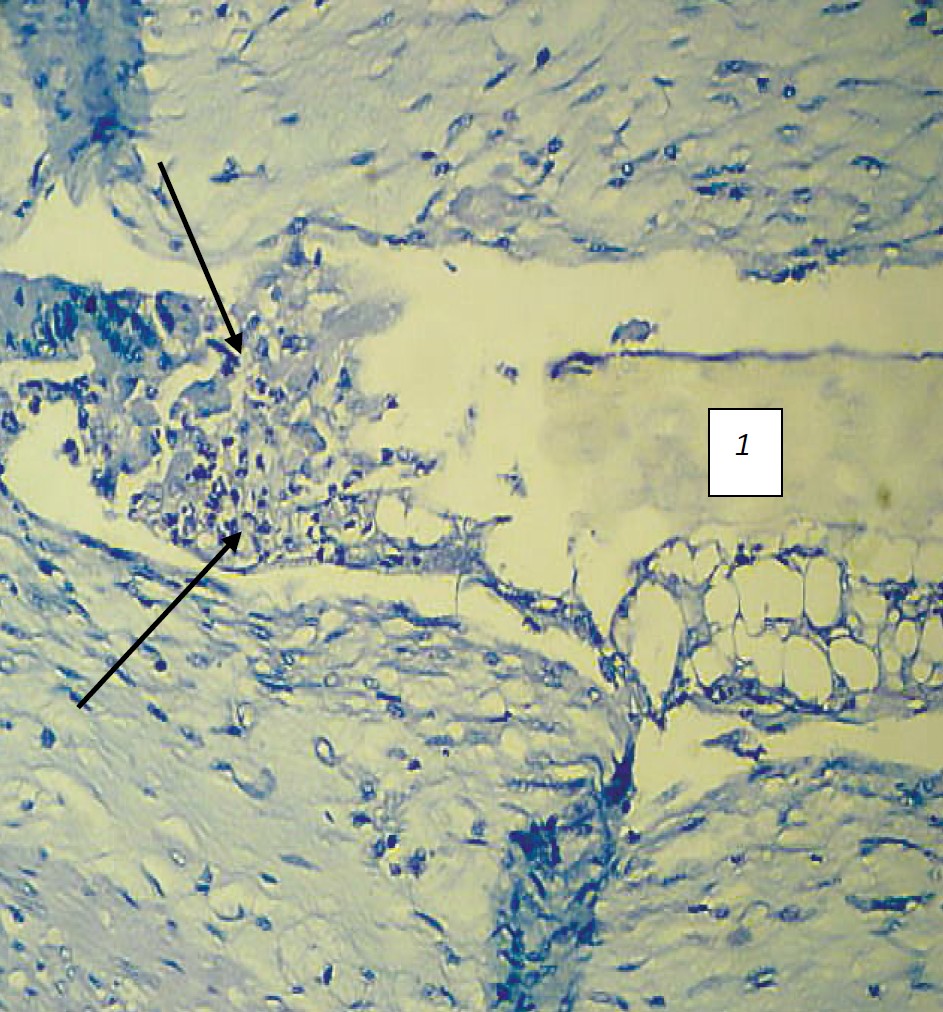

Рис. 5. Микроморфологическая картина стенки желудка кролика из группы 1 (латексный тканевый композит) на 7‑е сутки эксперимента: 1 — нить (указана стрелкой); 2 — полости в области расположения нити. Альциановый синий, ×100

Источник: выполнено К.Т. Инапшба, М.Д. Качалиным, Е.Н. Борхуновой, Н.В. Кислиновской.

Fig. 5. Micromorphological structure of the stomach wall of a rabbit from group 1 (latex tissue composite) on the 7th day of the experiment: 1 — thread (indicated by arrow); 2 — cavities in the area of the thread placement. Alcian blue, ×100

Source: complied by K.T. Inapshba, M.D. Kachalin, E.N. Borkhunova, N.V. Kislinovskaya.

На 7‑е сутки в экспериментальной группе 1 наблюдается сопоставление краев слизистой оболочки, однако небольшой диастаз в области расположения клеевого композита, а также в области расположения нити в мышечной и серозной оболочках по-прежнему сохраняется. Наблюдается умеренная воспалительная инфильтрация (рис. 5).